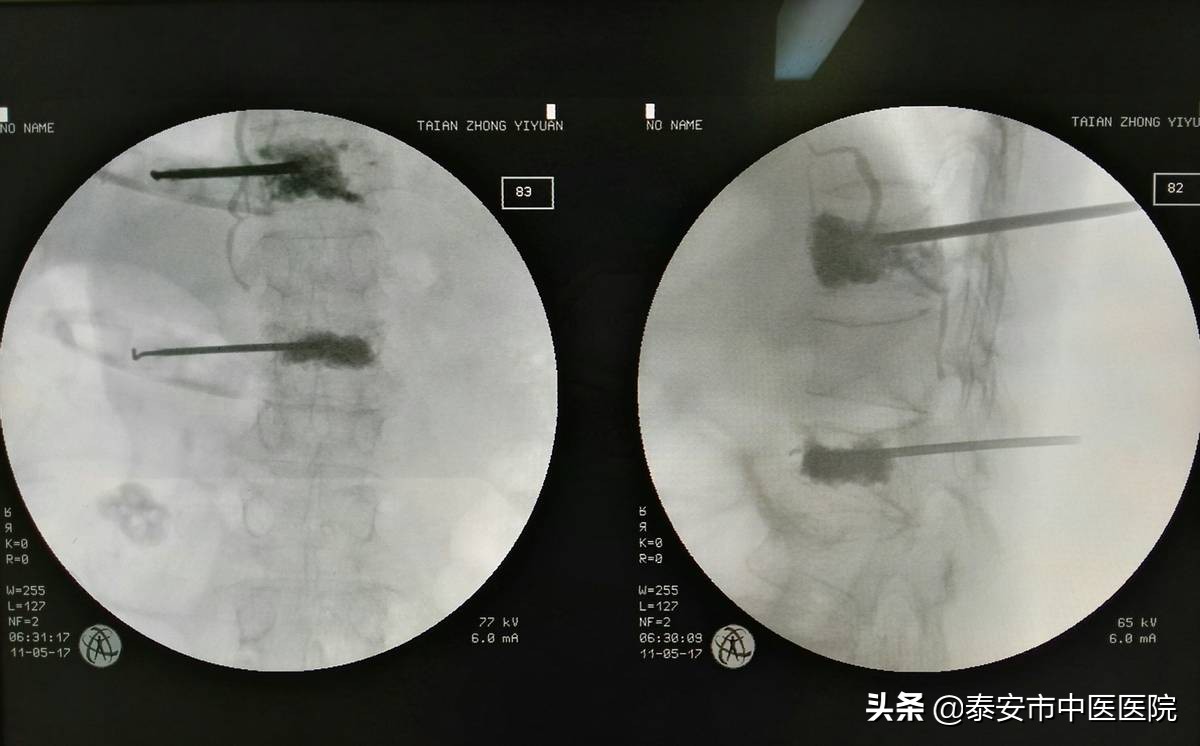

*安泰**市中医医院(*安泰**市骨伤医院)创伤骨科、手足外科开展“手法复位闭合穿针”技术治疗四肢骨折,具有不需切开,创伤小、痛苦少、复位固定牢靠、恢复快、花费少、不需二次手术取内固定等优点。此技术开拓了医院骨折微创治疗的新领域,使众多患者避免了开放手术所带来的弊端。骨科手术微创化已成为重要的发展的趋势,脊柱微创技术——椎体成形术目前该科室已成功开展100余例,术后半小时即可下地,术后第二天即可出院,改善患者生活质量优势显著,效果优良,均无并发症发生。

微创经皮椎体成形术治疗脊柱疾患